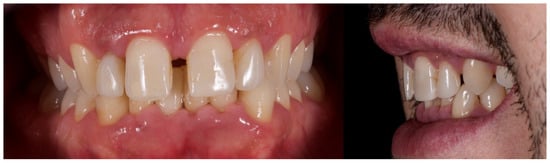

The patient was subsequently enrolled in a structured periodontal and prosthetic maintenance programme, with follow-up evaluations scheduled at four-month intervals to monitor periodontal health, occlusal stability, and the integrity of the prosthetic components (Figure 18, Figure 19 and Figure 20).

Figure 18. Final intraoral image.

Figure 19. Intraoral image at four-year follow-up.

At the four-year follow-up, clinical evaluation demonstrated stable soft and hard tissues, with no biological or mechanical complications observed throughout the entire follow-up period.

At the four-year follow-up, the clinical situation remained stable and asymptomatic. Periodontal evaluation revealed probing depths within physiological limits, a low plaque index (7%), and minimal bleeding on probing (8%), all consistent with a healthy periodontal environment. Radiographic assessment confirmed the maintenance of alveolar bone levels without signs of resorption. The patient’s reduction in tobacco use and adherence to four-month maintenance therapy intervals likely played a pivotal role in sustaining these outcomes. The four-year follow-up also confirmed the clinical stability of the treatment, both occlusally and periodontally, with a significant improvement in clinical indices and complete patient satisfaction. Masticatory function remained effective, the deep bite was corrected, and the interincisal diastema was successfully closed, resulting in a harmonious and stable aesthetic outcome. The final decision to fabricate individual crowns was justified by the favourable tissue response and the occlusal stability achieved.